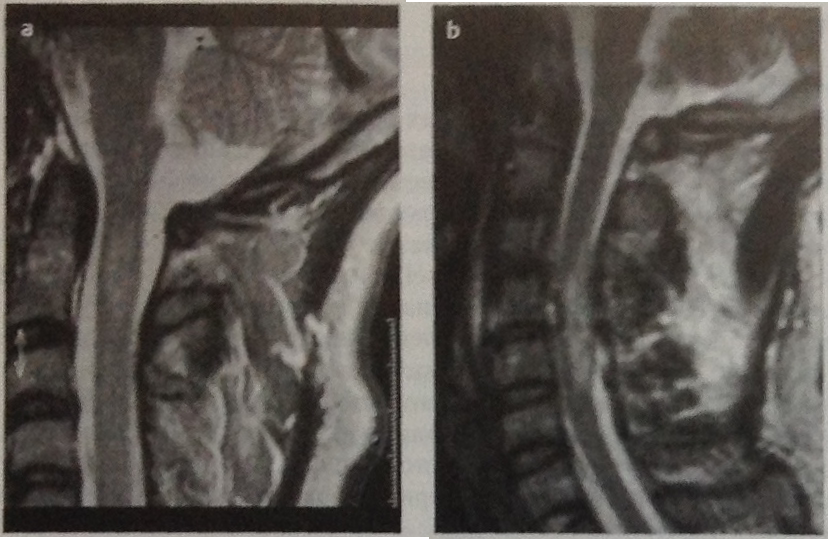

(Слева) Т2-ВИ, сагиттальная проекция: флексионное повреждение шейного отдела позвоночника с вывихом C5 и расхождением дуг С5-С6 позвонков. Имеется выраженный стеноз спинномозгового канала с контузией и сдавлением шейного отдела спинного мозга. Небольшой гипоинтенсивный очаг в спинном мозге представляет собой фокальное паренхиматозное кровоизлияние.

(Справа) STIR МР-И, сагиттальная проекция: случай врожденного стеноза спинномозгового канала и прогрузи и диска СЗ-С4 с компрессией спинного мозга. Пациент обратился с жалобами на слабость в верхних конечностях, возникшую после травмы. Обратите внимание на фокальный очаг контузии спинного мозга.

(Слева) На сагиттальном STIR МР-И пациента с диагностированным переломом зубовидного отростка II типа выявлены признаки распространенного отека превертебральных тканей. В паренхиме спинного мозга виден фокус кровоизлияния, представляющий собой очаг гипоинтенсивного сигнала, окруженный распространяющейся краниально и каудально зоной отека центральной части спинного мозга.

(Справа) На сагиттальном T2*GRE пациента с взрывным переломом С5 визуализируется распространенный гипоинтенсивный очаг в толще спинного мозга от уровня СЗ-С4 до середины тела С6, представляющий собой гематому.